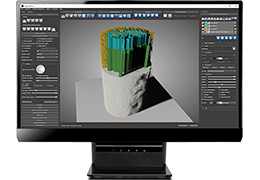

Performs 3D reconstruction and volume rendering.

Instant and interactive surface extraction and export to STL and PLY formats.

High-quality and fast 3D reconstruction and 3D rendering